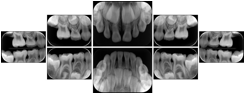

2. A patient requests cosmetic surgery to enhance their facial appearance. The case requires consultation between an orthodontist in New York and an oral surgeon in California. The cephalometric series of 2D projections constructed from the volumetric CT data that is used for the discussion is arranged by a Structured Display for transfer between the two practitioners.

Cephalometric Series Structured Display

Figure OO-2. Cephalometric Series Structured Display